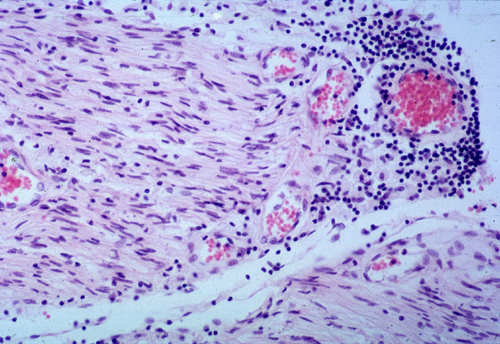

" التشخيص من خلال عينة - خزعة - من العضلات والاعصاب

GBSA (2).jpg

GBSA (3).jpg